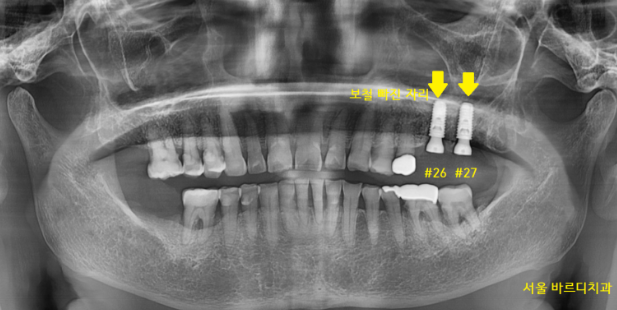

검진을 위해 X-RAY를 촬영해 보았더니

보철 수명이 다 된 것이 보이네요~

두 가지 문제가 있었습니다.

첫번째, 잇몸도 많이 내려가

맨 끝 치아는 흔들려 강일역 임플란트가 필요

두번째, 보철을 씌운 치아는 충치가 생긴 게 확인이 됩니다.